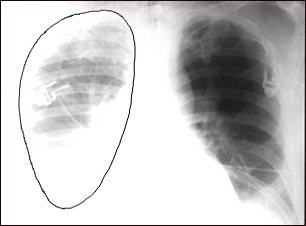

Ruptura aórtica, radiografía de tórax

En esta imagen se puede apreciar una ruptura aórtica (rompimiento de la aorta, arteria mayor que viene del corazón). En este caso, la causa es una perforación traumática de la aorta torácica. Así aparece la radiografía cuando el tórax está lleno de sangre (hemotórax del lado derecho), visto aquí como una nubosidad al lado izquierdo de la imagen.